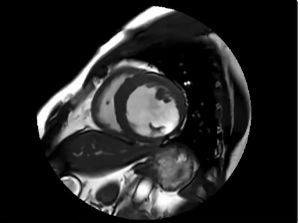

二:临床申请单:心脏MR平扫加增强 2.1 心脏电影成像FIESTA Cine

4CH FIESTA Cine目测还好,问题不大。

SA FIESTA Cine:左心室下侧壁非常薄,和一张纸糊的一样。此处毗邻胃,会不会是胃内气体导致的磁敏感伪影?